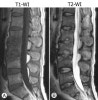

3. MRI

정확하고 빠른 효과적인 진단 수단

단, pyogenic과 non-pyogenic infection을 감별할 수 없으므로 조직 생검의 필요성을 줄이지는 못합니다.

추체와 그 사이의 추간강 부위는 T2 강조영상에서는 신호강도 증가, T1 강조영상에서는 신호강조 감소되어 경막 외 확장이나 연부조직 농양의 윤곽을 나타내는 데 유용합니다.

MRI : 척추 감염(Spinal infection)